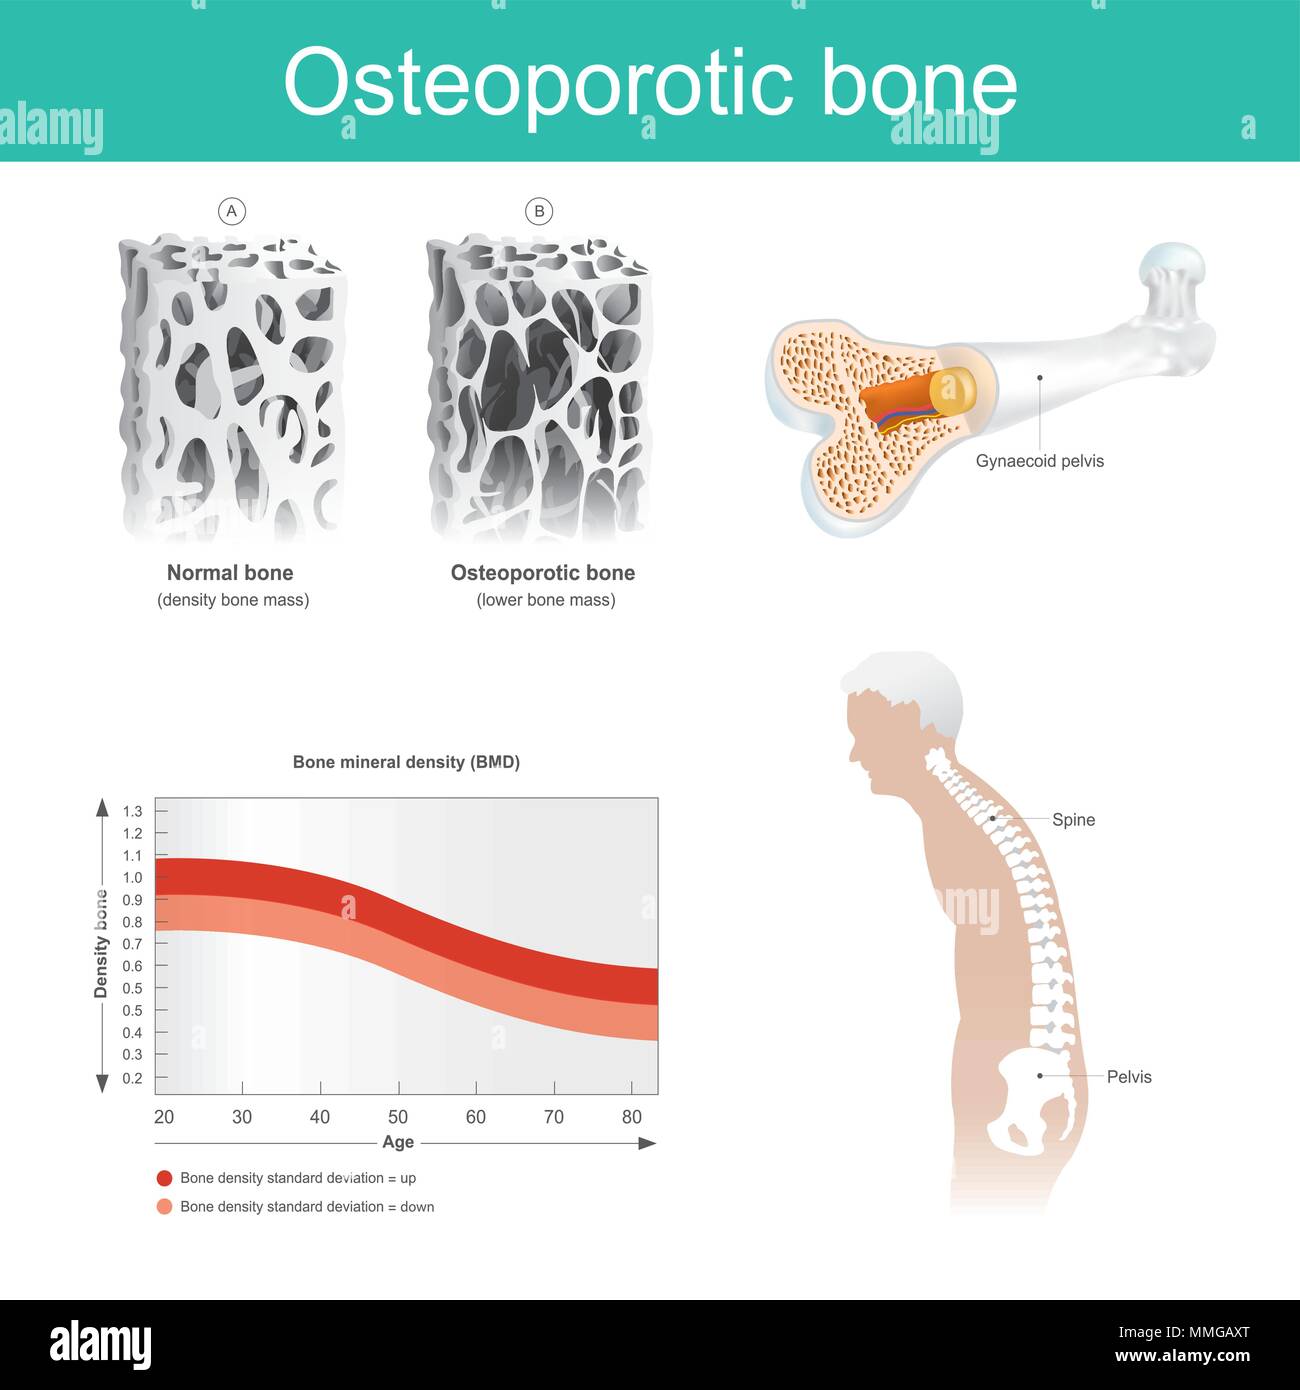

Questa è una malattia in cui la densità e la qualità del tessuto osseo sono ridotti. Il vecchio uomo salute si è deteriorata a causa della mancanza di calcio. Illustrazione Vettorialehttps://www.alamy.it/image-license-details/?v=1https://www.alamy.it/questa-e-una-malattia-in-cui-la-densita-e-la-qualita-del-tessuto-osseo-sono-ridotti-il-vecchio-uomo-salute-si-e-deteriorata-a-causa-della-mancanza-di-calcio-image184756624.html

Questa è una malattia in cui la densità e la qualità del tessuto osseo sono ridotti. Il vecchio uomo salute si è deteriorata a causa della mancanza di calcio. Illustrazione Vettorialehttps://www.alamy.it/image-license-details/?v=1https://www.alamy.it/questa-e-una-malattia-in-cui-la-densita-e-la-qualita-del-tessuto-osseo-sono-ridotti-il-vecchio-uomo-salute-si-e-deteriorata-a-causa-della-mancanza-di-calcio-image184756624.htmlRFMMGAXT–Questa è una malattia in cui la densità e la qualità del tessuto osseo sono ridotti. Il vecchio uomo salute si è deteriorata a causa della mancanza di calcio.